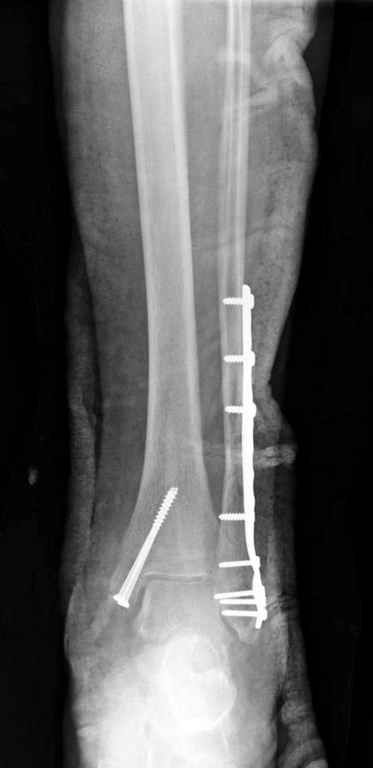

Здесь финальный снимок 73 летней с

сопутствующей шизофренией, латерально бридж

пластину (соединили дистальный конец с диафизом не трогая место перелома) и медиально перкутанно

двумя шурупами. В этам случае без гипса не

обойтись.